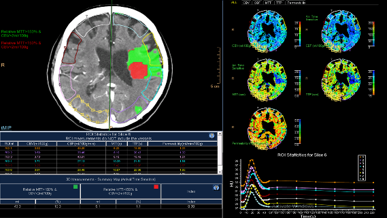

Advancing care for the body’s most complex organ

With the aging population, neurodegenerative disease is on the rise worldwide. Since neurological disorders are often chronic, patients require long-term follow-up, but changes in the brain can be subtle and hard to detect. IntelliSpace Portal 9.0 offers a host of new and enhanced neuro applications such as NeuroQuant®², LoBi¹ and CT Brain Perfusion. These tools are designed to facilitate rapid, objective, quantitative and consistent image evaluation. - Manage pulmonary patients with just o... || KBA1

Advancing care for the body’s most complex organ

With the aging population, neurodegenerative disease is on the rise worldwide. Since neurological disorders are often chronic, patients require long-term follow-up, but changes in the brain can be subtle and hard to detect. IntelliSpace Portal 9.0 offers a host of new and enhanced neuro applications such as NeuroQuant®², LoBi¹ and CT Brain Perfusion. These tools are designed to facilitate rapid, objective, quantitative and consistent image evaluation. - Manage pulmonary patients with just o... || KBA1

Streamline your clinical workflow

IntelliSpace Portal 9.0 delivers an advanced suite of clinical applications, with a focus on neurodegenerative disease. Neuro applications for longitudinal patient1 assessment facilitate rapid, objective, and quantitative image interpretation, even for subtle changes. IntelliSpace Portal also includes an enhanced cardiovascular portfolio, plus new technical innovations such as machine learning. This single comprehensive platform helps you meet your Advanced Visualization needs.

Discover new insights into the body’s most complex organ with a new longitudinal and comparative application optimized for neurology and integration of the NeuroQuant®2 application. Plus, we’ve added a suite of CT spectral applications for use with the IQon Spectral CT scanner.